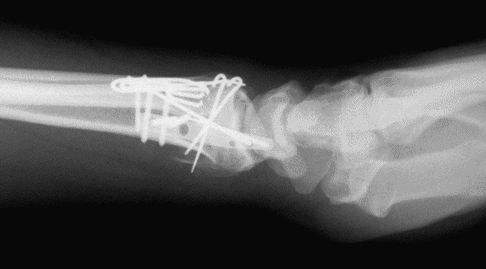

Case 1 Postop